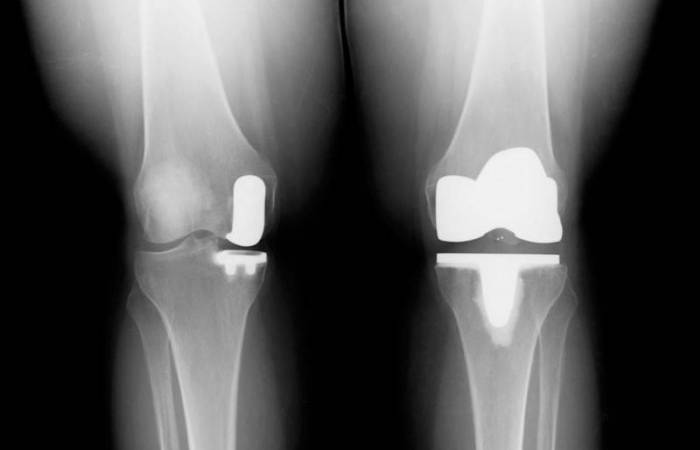

На фото — две ноги одного пациента: слева операция была проведена частично, справа — полностью.